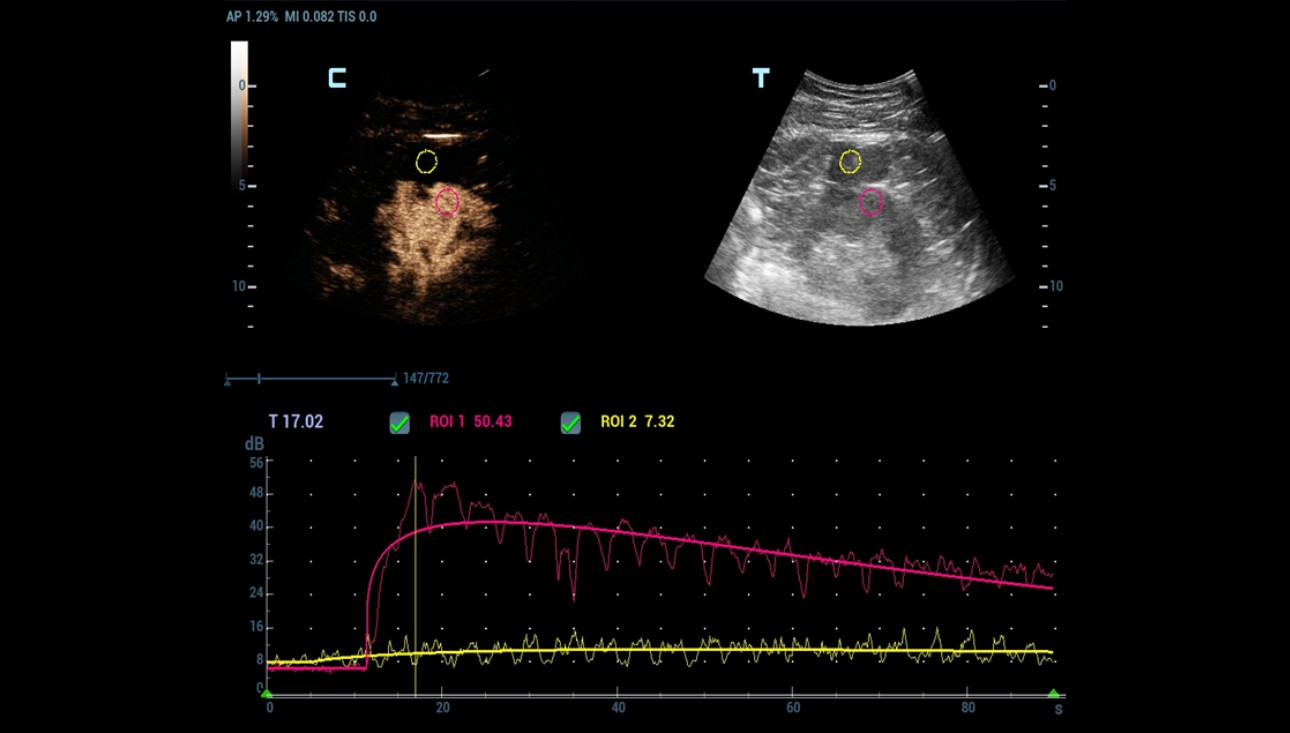

As Power Doppler showed indeterminate results regarding internal flow within the complex cystic mass, CEUS was performed through injection 1.2 ml of Sonovue (Bracco Swiss, SA, Switzerland). The longitudinal plane of the kidney with the maximum section of the cystic mass was selected for scanning. At the end, the cystic mass was characterized as benign by a lack of enhancement throughout the CEUS study (Figure 4 and 5).

Quantitative analysis also confirmed the absence of enhancement within the cystic mass (Figure 6).